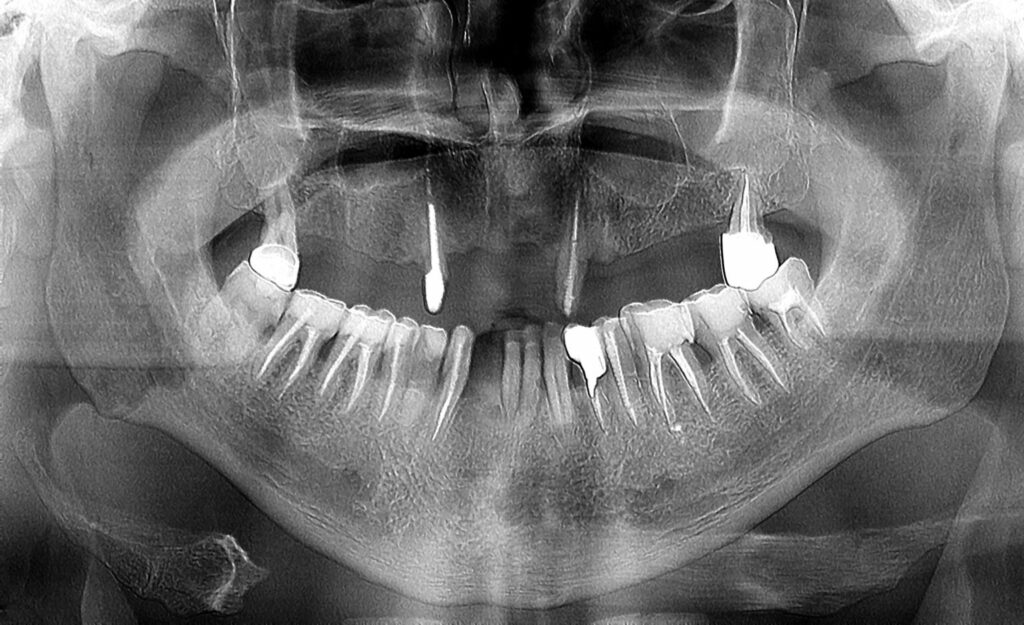

Фотографии и схемы для ОПТГ и мезиального прикуса